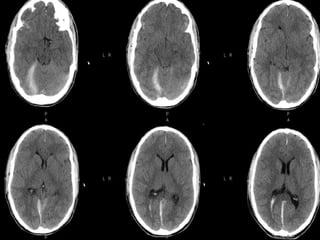

DIFFUSE AXONAL INJURYDIFFUSE AXONAL INJURY

Rarely detected on CT ( 20% of DAI

lesions are hemorrhagic)

MRI:T1,T2,T2 GRE, SWI

DAIDAI

Due to acceleration/deceleration to

whtie matter + hypoxia

Patients have severe LOC at impact

Grade 1: axonal damage in WM only -67%

Grade 2:WM + corpus callosum

(posterior > anterior) – 21%

Grade 3:WM + CC + brainstem

Hours:

◦ hemorrhages and tissue tears

◦ Axonal swellings

◦ Axonal bulbs

Days/weeks: clusters of microglia and

macrophages, astrocytosis

Months/years:Wallerian degeneration

DIFFUSE AXONAL INJURYDIFFUSEAXONAL INJURY Rarely detected on CT ( 20% of DAI lesions are hemorrhagic) MRI:T1,T2,T2 GRE, SWI

DAIDAI Due to acceleration/decelerationto whtie matter + hypoxia Patients have severe LOC at impact Grade 1: axonal damage in WM only -67% Grade 2:WM + corpus callosum (posterior > anterior) – 21% Grade 3:WM + CC + brainstem

DAIDAI Hours: ◦ hemorrhages andtissue tears ◦ Axonal swellings ◦ Axonal bulbs Days/weeks: clusters of microglia and macrophages, astrocytosis Months/years:Wallerian degeneration